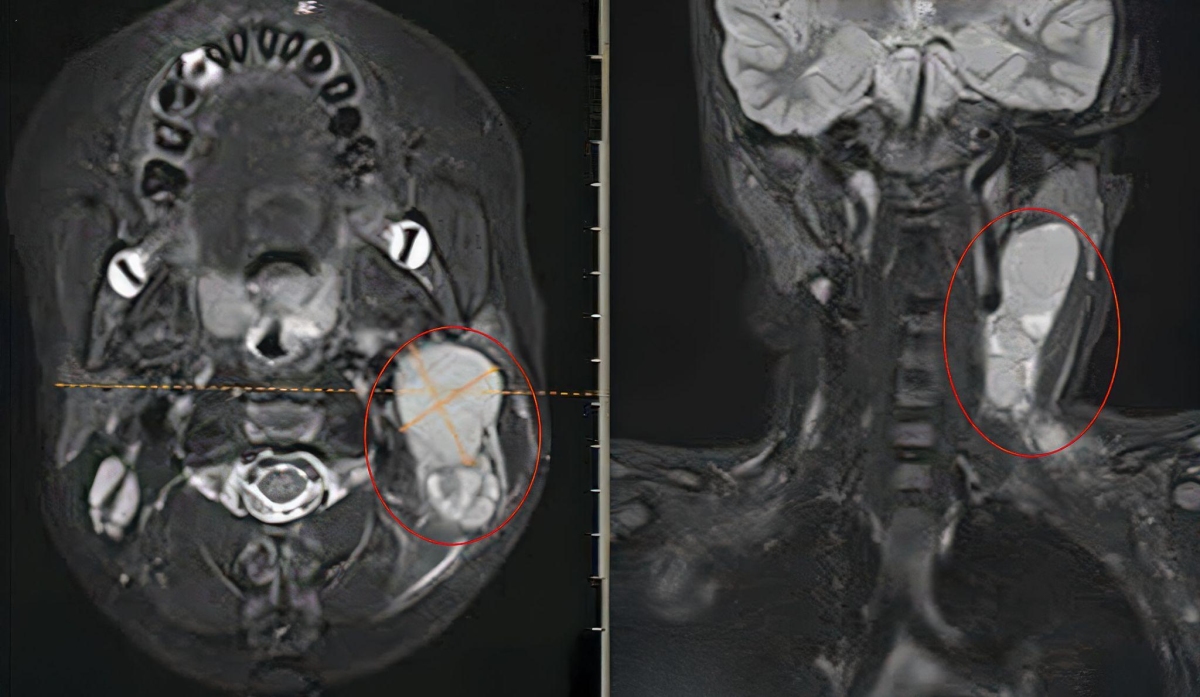

Một tháng trước, cổ bé Trí xuất hiện khối u kích thước khoảng 2 cm. Khi u to gấp 4 lần, gia đình đưa bé đến Bệnh viện Đa khoa Tâm Anh TP HCM xét nghiệm và chụp X-quang, MRI, bác sĩ nghi ngờ lymphoma hoặc hạch lao, kê đơn thuốc kháng sinh và kháng viêm uống. Sau ba ngày, bệnh nhi kháng thuốc, khối u tiếp tục sưng to hơn chiếm 1/2 vùng cổ gây đau, bác sĩ phẫu thuật bóc tách hạch và sinh thiết tìm nguyên nhân.

Kết quả chụp MRI cho thấy khối hạch ở vùng cổ bệnh nhi. Ảnh: Bệnh viện Đa khoa Tâm Anh